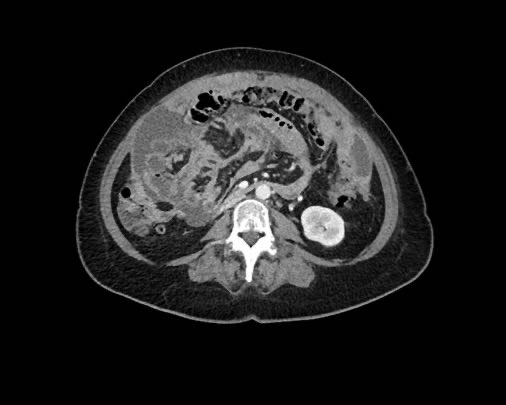

Ca lâm sàng 1

Cuộn qua các lát cắt.

Bạn có thể phát hiện tất cả các tổn thương cấy ghép phúc mạc không?

Bệnh nhân này đã được phẫu thuật và toàn bộ phúc mạc được ghi nhận phủ kín bởi các tổn thương u dạng kê.